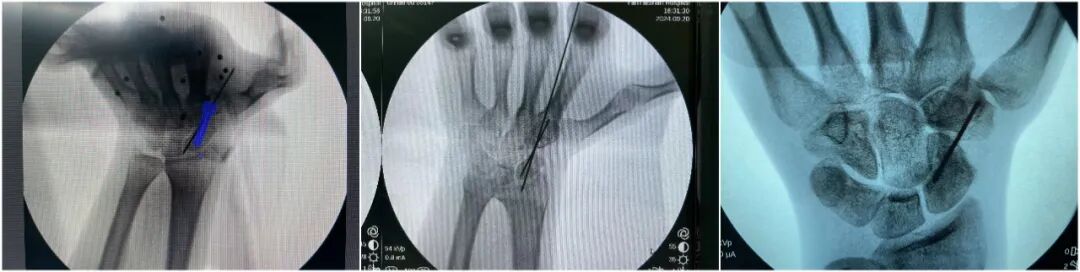

手术方案由李晓副主任医师、徐俊涛主治医师负责施行。术中通过骨科机器人进行精准定位,复位舟骨骨折,交叉钛针固定后,术中透视效果满意,留置导针;应用腕关节镜,成功建立MCR和MCU入路,见骨折端硬化,局部滑膜增生,清理增生滑膜,磨钻磨除硬化骨至新鲜骨折面,取对侧髂骨松质骨,镜下植入折端,压实后经导针引导拧入可吸收空心钉,术中透视,骨折内固定位置理想,折端植骨充分,手术顺利完成。腕背部仅有两处不足2mm的微小切口。